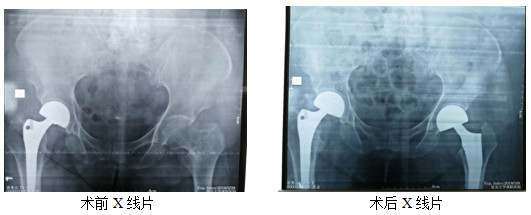

近日,患者姜某某,女性,76歲,因摔傷致左側(cè)髖部疼痛4小時(shí)入院,行拍片,診斷:左側(cè)粗隆間粉碎骨折。因患者年齡偏大,體重較重,右側(cè)于入院前兩年在外院行關(guān)節(jié)置換手術(shù)。家屬慕名來骨科一病區(qū)就診。入院后,立即給予對(duì)癥處理,完善各項(xiàng)術(shù)前評(píng)估,并于傷后第3天行手術(shù)治療。過去術(shù)后一個(gè)半月左右才允許患者下床活動(dòng)?,F(xiàn)在患者麻醉清醒后就開始患肢活動(dòng),術(shù)后3天,逐漸在下肢助行器的輔助下進(jìn)行完全負(fù)重活動(dòng)。對(duì)比上次外院手術(shù)、康復(fù)情況及就醫(yī)體驗(yàn),患者及家屬表示非常滿意。

骨科一病區(qū)在創(chuàng)傷、關(guān)節(jié)、骨病、脊柱、足踝肩肘外科等骨科領(lǐng)域的治療方面具有豐富的臨床經(jīng)驗(yàn)。可開展各種復(fù)雜四肢骨折及關(guān)節(jié)內(nèi)骨折、脫位的手法及手術(shù)治療;全髖關(guān)節(jié)及全膝關(guān)節(jié)置換術(shù);骨不連、急慢性骨髓炎、關(guān)節(jié)炎的手術(shù)治療。脊柱骨折脫位并截癱的手術(shù)治療。頸、胸、腰椎間盤突出癥、椎管狹窄癥的手術(shù)治療。四肢骨腫瘤的手術(shù)治療。近年來,科室開展了復(fù)雜髖關(guān)節(jié)病變?nèi)y關(guān)節(jié)置換術(shù)、椎管內(nèi)占位性病變的手術(shù)治療 、骨關(guān)節(jié)炎的保髖、保膝治療等,均具市內(nèi)先進(jìn)水平。